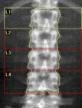

Wir betrachtens es als eine unserer ärzlichen Aufgaben, Erkrankungen des Knochens möglichst früh zu erkennen und zu behandeln. Dabei orientieren wir uns an den Leitlinien der Dachgesellschaft für Osteologie (DVO) und deren Qualitätskriterien. Die Knochendichtemessung mittels der DEXA-Methode ist eine technische Standarduntersuchung zur Erkennung von Knochenmineralverlusten. Wir bieten diese Untersuchung in unserer Praxis an.